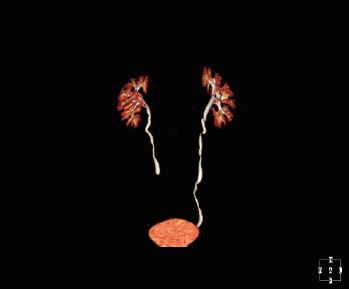

Умное рабочее место медицинского отображения

Согласно международному стандарту DICOM 3,0, само-разработанное рабочее место CIW совершенно исполняет с

стандарты медицинских изображений, включая функции получать, обрабатывающ, анализирующ, управляющ, помещающ в архив

запрашивающ, просматривающ, печатающ стандартный выход формата изображения, сочинительство отчета и так далее. В то же время, CIW также

содержит много других предварительных клинических применений.